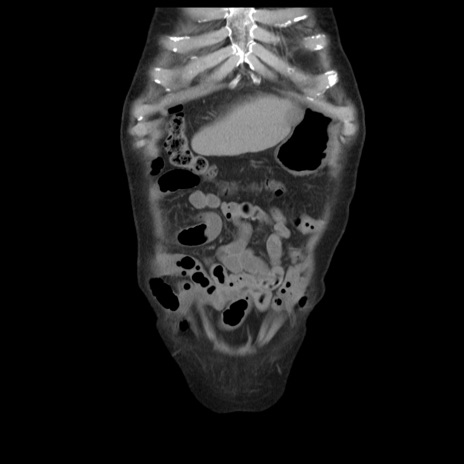

症例21(冠状断像)

【症例】70歳代男性

【主訴】腹痛

【現病歴】肝硬変・肝細胞癌にてかかりつけの方。約9時間前に食後より腹痛出現。症状が徐々に増悪し、嘔吐出現したため来院。

【既往歴】肝硬変、肝細胞癌(RFA、TACE後)

【身体所見】意識清明、表情苦悶様、BT 36℃、BP 129/78mmHg、P 88bpm、SpO2 97%(RA)、右上腹部から心窩部にかけて圧痛あり、反跳痛なし、筋性防御あり。

【データ】WBC 5800、CRP 0.16